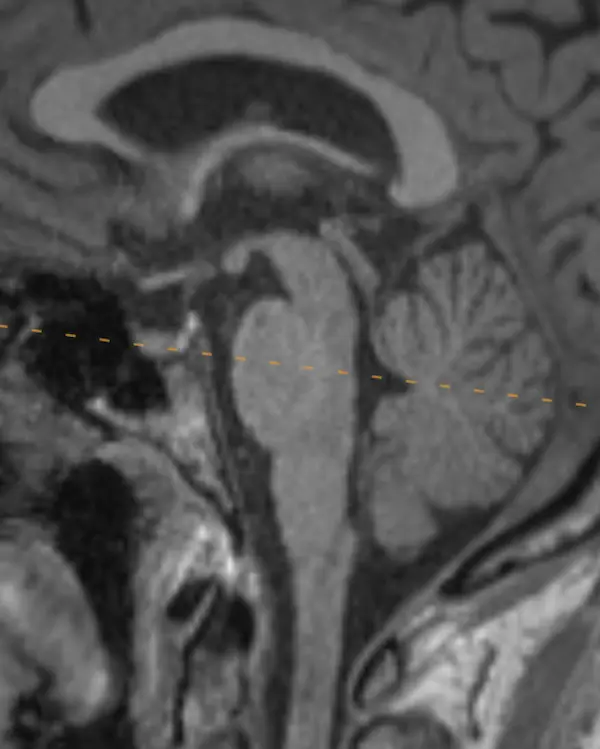

Note that axial planes in brain imaging are not perfectly perpendicular to the brainstem, they are instead created by drawing a line through the anterior commissure (AC) and posterior commissure (PC); the so-called AC-PC line. Keep this in mind when correlating the appearance of structures in the axial plane to sagittal.

5. Trigeminal nerve (CN V)

The trigeminal nerve is the largest cranial nerve. It exits the side of the pons approximately one slice above the internal auditory canals, then curves forward to traverse the CSF space in front of the pons called the prepontine cistern. It primarily provides sensory innervation to the face, mouth, anterior two thirds of the tongue, nasal sinuses, and dura mater. It has a smaller contribution to motor function of the muscles of mastication.

The trigeminal nerve is large enough to be at least partially visible on routine brain MRIs, though it is sometimes cut off or volume averaged along its course. Notice the image below looks slightly different. This is a heavily T2-weighted sequence with thin slices that is designed to maximize the contrast between CSF and CSF-surrounded structures, usually cranial nerves, blood vessels, or extra-axial lesions. These heavily T2-weighted sequences are useful for ruling out the most common identifiable cause of trigeminal neuralgia: compression by a blood vessel (i.e. neurovascular compression). The region of a cranial nerve most susceptible to symptomatic compression is called the transition zone (aka Obersteiner-Reidlich zone), which is a few millimeters-long gradient of transition from oligodendrocyte myelination (central) to Schwann cells (peripheral). These transition zones are close to where the nerve emerges from the brainstem, called the root entry zone. For the trigeminal nerve, it is 3-4 mm away.

The trigeminal nerve has four nuclei, and two are located around this level.

Trigeminal Nerve in Sagittal

The two most important trigeminal nuclei are the main sensory and motor nuclei, introduced above. The mesencephalic and spinal nuclei are elongated and span the majority of the brainstem. Their approximate location in the axial plane will be introduced in the next level.

The name trigeminal comes from its three divisions: ophthalmic (V1), maxillary (V2), and mandibular (V3). This split occurs at the trigeminal ganglion, located in a CSF space beside and below the cavernous sinus called Meckel's cave.